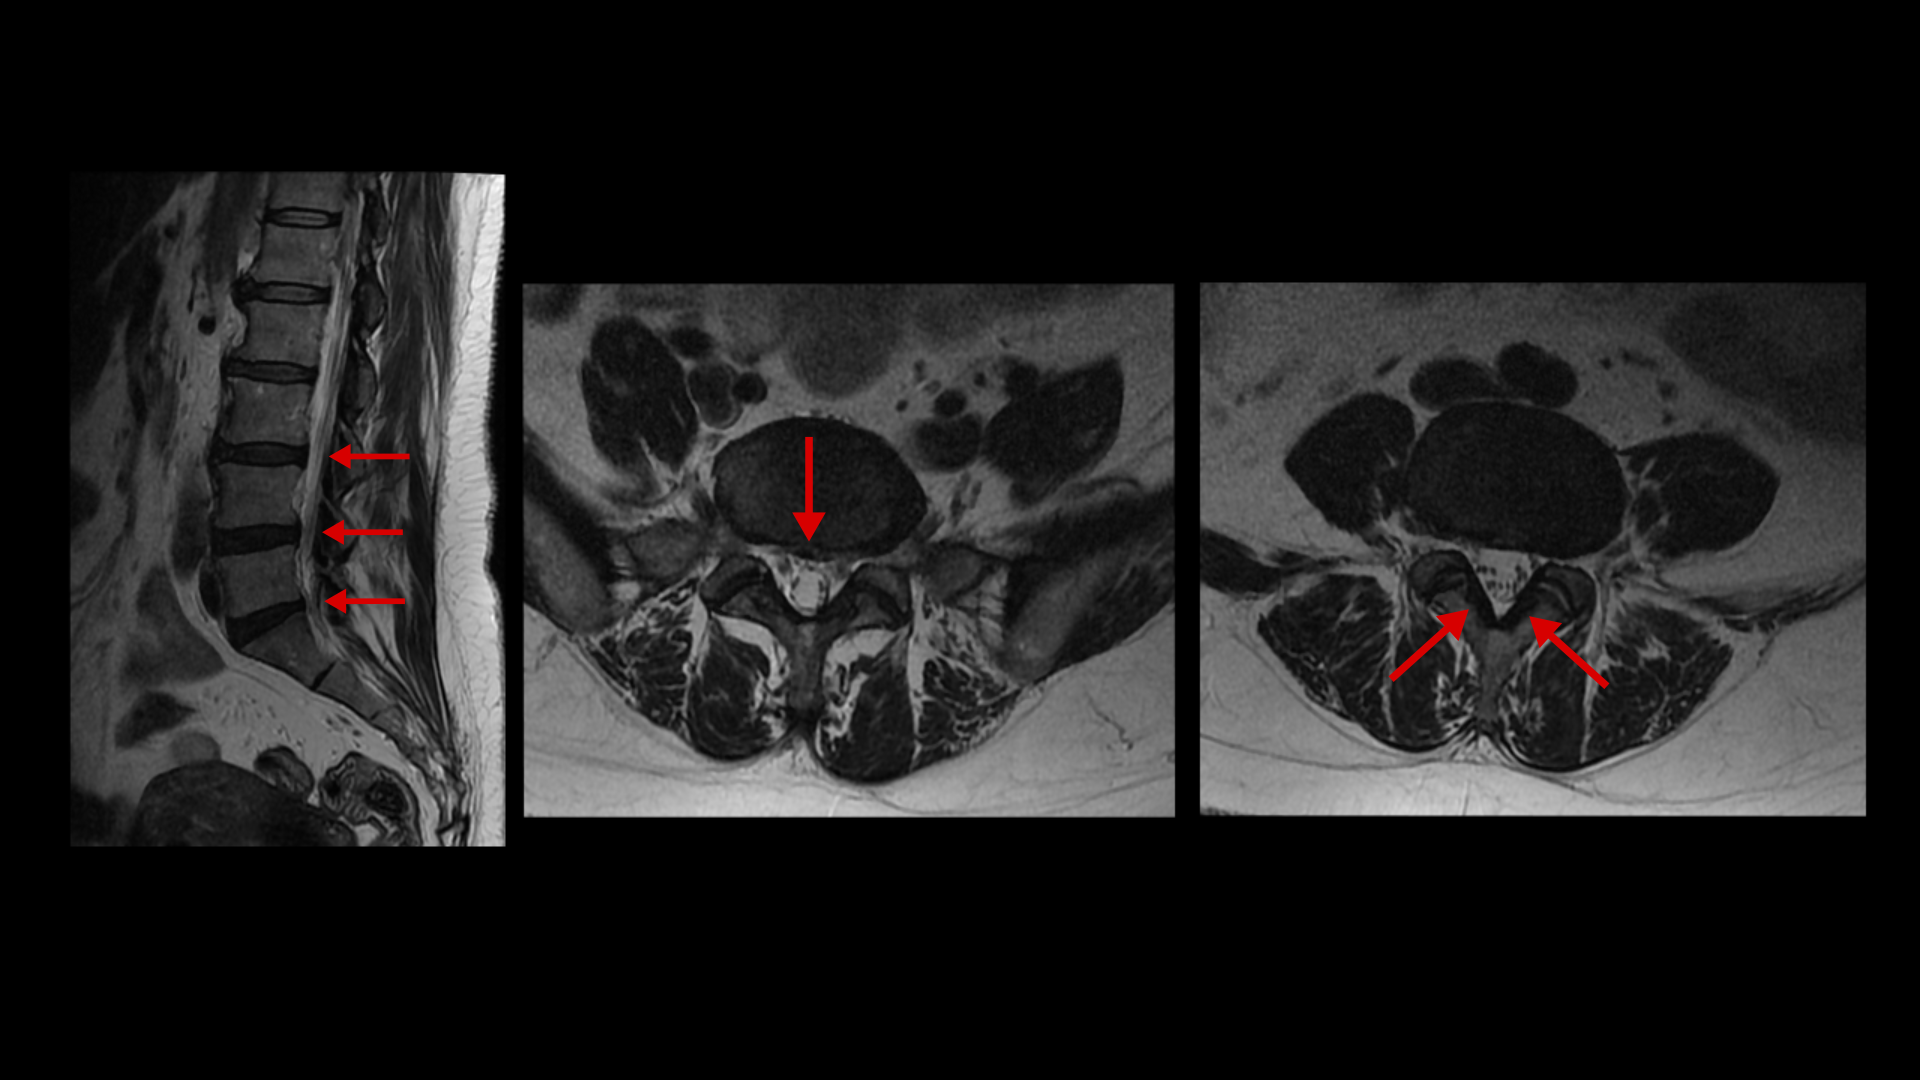

이분 MRI를 보면 퇴행성 변화가 있기는 합니다.

퇴행성 디스크와 디스크 돌출이 있고 황색인대의 비후도 있지만 신경을 심하게 누르는 게 보이지 않기 때문에 양쪽 다리에 감각마비가 올 정도의 심한 신경학적 증상을 일으키기는 어렵다고 봅니다. MRI와 이 환자의 증상이 일치하지 않는 겁니다. 이 환자분의 극심한 증상을 MRI로 설명할 수가 없는 겁니다.

날씨만 안 좋아도 아예 일어서지를 못하셨다고 합니다. 이분처럼 허리와 다리가 저리고 아픈데 MRI에 퇴행성 디스크나 협착이 조금이라도 보이면 거의 대부분 디스크나 협착으로 진단하고 그것을 치료하게 됩니다. 그런데 이분 MRI에서 보시다시피 양쪽 다리에 심한 신경학적 증상을 일으킬만한 병변이 보이지 않습니다. 그래서 반드시 증상과 MRI가 일치하는지 꼼꼼하게 확인하는 게 필요합니다. 진단이 잘못되면 증상의 원인이 아닌 협착증이나 디스크 치료를 한다고 시간만 낭비하고 오랫동안 고생 하기 쉽습니다.